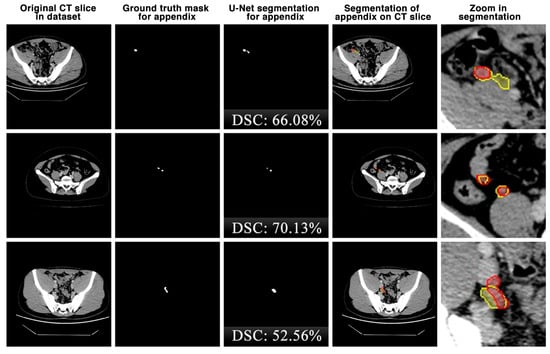

The appendix regions successfully detected and segmented on CT slices using the proposed U-Net deep learning architecture during the experimental studies are shown in Figure 6. While the mask of an original CT slice in Figure 6a containing the appendix region delineated by the expert is shown in Figure 6b, the segmentation of the appendix by the proposed U-Net deep learning architecture is shown in Figure 6c along with the DSC score. On the other hand, the overlap of the expert mask and the U-Net segmentation on the CT slice is also shown in Figure 6d and its zoomed version is shown in Figure 6e. As can be seen, the proposed U-Net-based deep learning architecture is very successful in segmenting the appendix CT scans and is very close to the expert GTs. Some examples of the segments that the proposed model has difficulty in detecting are shown in Figure 7. When analysing Figure 7, it is clear that the model cannot successfully detect some slices. The lack of success in these slices can be attributed to the fact that the appendix region is close to or adjacent to other areas, or the boundaries of the region are similar to those of the neighbouring areas. Such cases stood out as instances where the boundaries of the appendix were blurred and the model was unstable.

Figure 7.

Some examples of unsuccessful appendix detection and segmentation by the proposed U-Net model. Red: ground truth mask for appendix, yellow: U-Net segmentation for appendix.